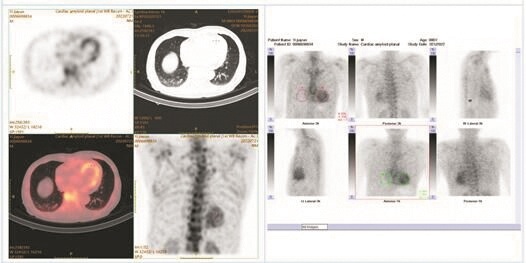

心脏彩超提示双房增大 图片由武汉大学人民医院提供

为王爹爹完善相关检查并调阅以往病例资料后,蒋学俊教授判断,王爹爹左右心房增大、室壁增厚、射血分数保留、心包腔积液,无法用缺血性心脏病和肥厚型心肌病的常规病理来解释,同时其肾功能受损也未找到合理病因——王爹爹的疾病恐怕另有隐情。

蒋学俊教授随即带领团队启动心肌病MDT诊疗流程,联合超声医学科、核医学科、肾内科等专家团队,确诊王爹爹患有转甲状腺素蛋白心脏淀粉样变(ATTR-CM,俗称“淀粉人”):淀粉样蛋白团块在王爹爹心脏中异样沉积,影响了心脏的正常功能,从而导致一系列病症。